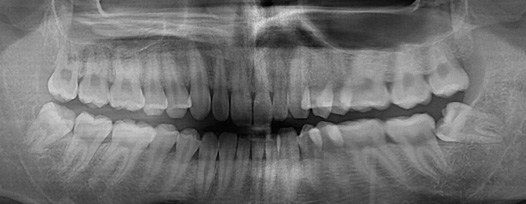

사랑니 발치

최소통증으로, 편안하게!

왜 청담네오플란트에서 사랑니를 뽑아야 할까요?

청담네오플란트는 3D CT 촬영 후 전문의료진들의 정확한 분석으로 안전하게 사랑니를 발치합니다.

매복 사랑니 발치 이젠 두려워하지 마세요!

사랑니를 뽑아야 하는 경우

통증이 없고 관리만 잘 된다면 무조건 사랑니 발치를 할 필요는 없습니다. 하지만 아래의 해당사항이 있는 경우 발치를 권장합니다.

01사랑니 또는 사랑니 앞의 어금니에 충치가 생긴 경우

02사랑니 주위의 잇몸이 주기적으로 붓고 통증이 생기는 경우

03사랑니 주위 잇몸뼈의 손상이 심한 경우

04돌출된 앞니의심미 보철을 위한 경우

05치아를 씌우기 위해 많이 깎아야 하는 경우

06과거의 신경치료가 실패하여 염증이나 통증이 재발한 경우

청담네오플란트치과 사랑니 발치 프로세스

01. CT 촬영

안전하고 통증을 최소화한 발치를 위해 3차원 정밀 분석을 합니다.

02. 정확한 분석

사랑니의 크기와 방향, 깊이, 뿌리 상태 등과 구강검진을 실시합니다.

03. 발치 전 상담

발치 후 주의사항 및 증상, 예후관리에 대한 자세한 상담을 진행합니다.

04. 발치 전 마취

발치 전 2단계 무통마취로 발치시 통증을 최소화하고 안전한 발치가 가능합니다.